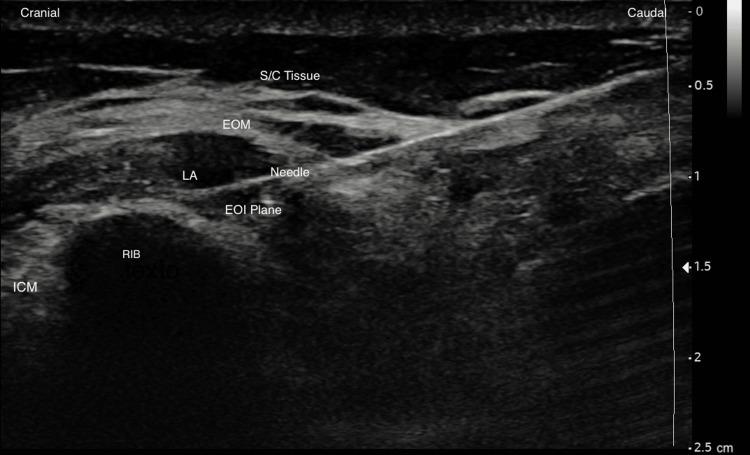

External Oblique Intercostal Block for Living Kidney Donor Open Nephrectomy: A Case Series.

The external oblique intercostal (EOI) block is a novel regional technique that provides analgesia for upper abdominal incisions. We performed single-injection and continuous EOI blocks in living kidney donors who underwent open nephrectomy. In this case series, we report our experience with pain management using this technique in five patients at our centre. EOI block resulted in good pain relief in our patients. The median (IQR) numerical rating scale score was 3 (1-6) at rest immediately after the end of the surgery, predominantly visceral. We want to highlight the benefits regarding pain management of the association of EOI block with conventional therapy.

腹外斜肌肋间(EOI)阻滞是一种新型区域技术,可为上腹部手术切口提供镇痛。我们对接受开放性肾切除术的活体肾供体进行了单次注射和连续EOI阻滞。在这个病例系列中,我们报告了我们中心5例患者使用该技术进行疼痛管理的经验。EOI阻滞在我们的患者中产生了良好的疼痛缓解效果。术后立即休息时,数字评分量表评分的中位数(IQR)为3(1-6),主要为内脏痛。我们想强调EOI阻滞与传统治疗联合在疼痛管理方面的益处。